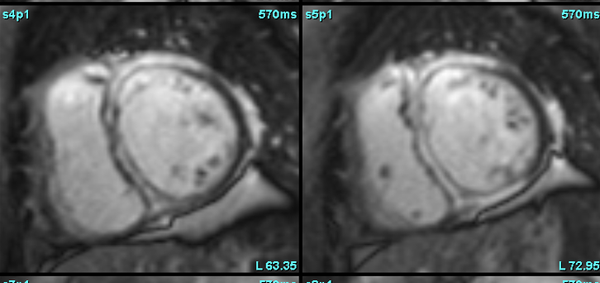

Amyloidosis